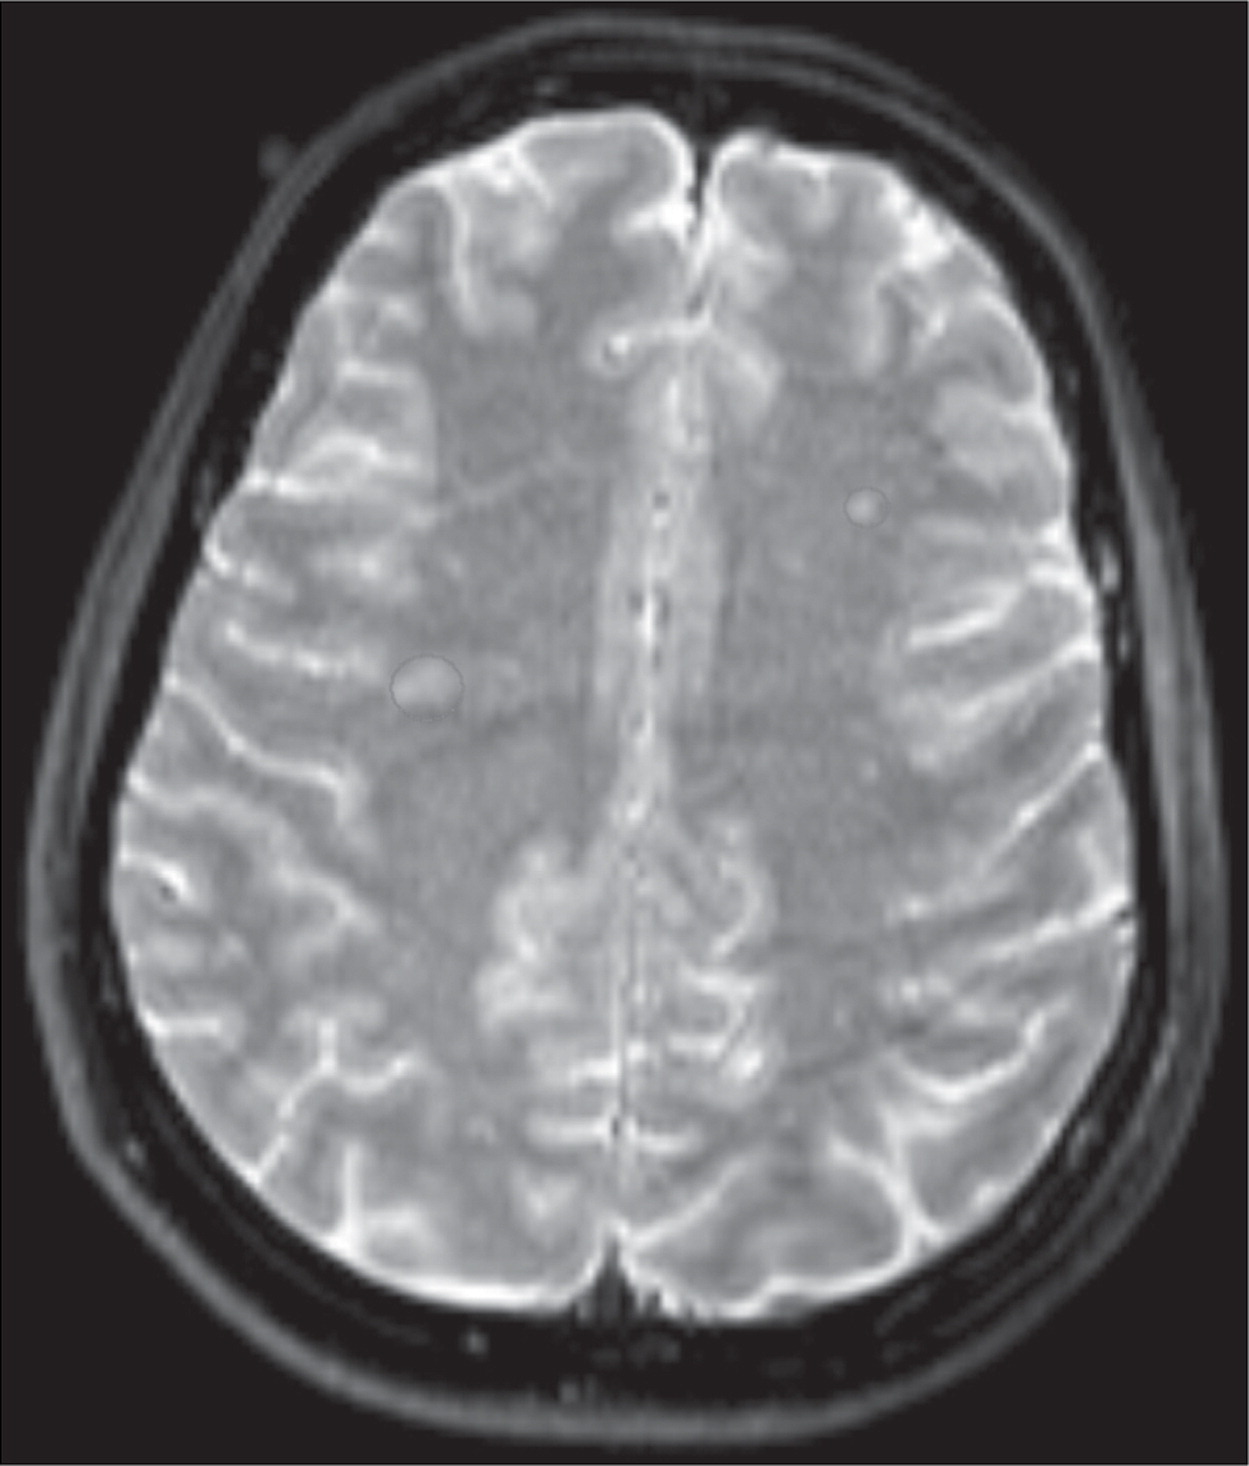

Ressonância magnética cerebral que mostra lesões de substância branca no centro semioval

Somente aos 52 anos ela decidiu procurar ajuda em uma clínica psiquiátrica em Haia. No início, os exames não mostraram anormalidades: sangue, eletroencefalograma e testes neurológicos pareciam dentro do esperado. Foi apenas por meio de uma ressonância magnética que surgiu uma pista. O exame revelou pequenas lesões na substância branca próxima ao núcleo lentiforme, região associada ao reconhecimento facial, à atenção e à memória.